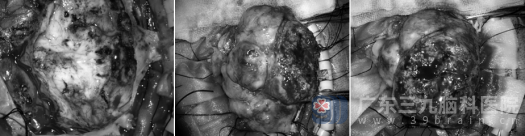

经过充分的术前准备,在欧阳辉教授和林德留主任的带领下为陈女士实施了肿瘤切除手术。手术历时5小时,在神经导航及显微技术的辅助下,团队凭借丰富的经验和精湛的显微操作技术,成功将肿瘤完整摘除,手术过程顺利。

术中情况